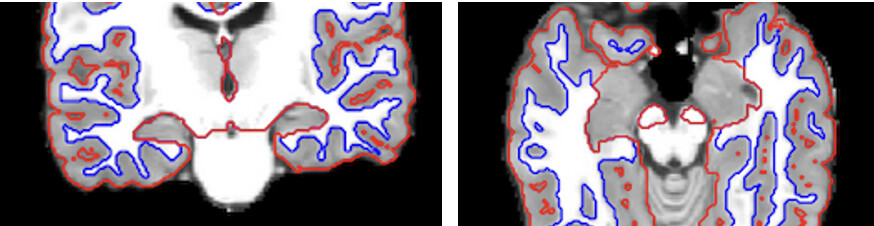

We are currently working on pre-processing our MRI data using fMRIPrep. In the reports, we noticed that in almost all subjects, the segmentation looks messy near the hippocampus. Since we are seeing this across all subjects, we were wondering whether this is a segmentation error or due to Freesurfer not including subcortical regions in the cortical segmentations. The same appears in the second picture.